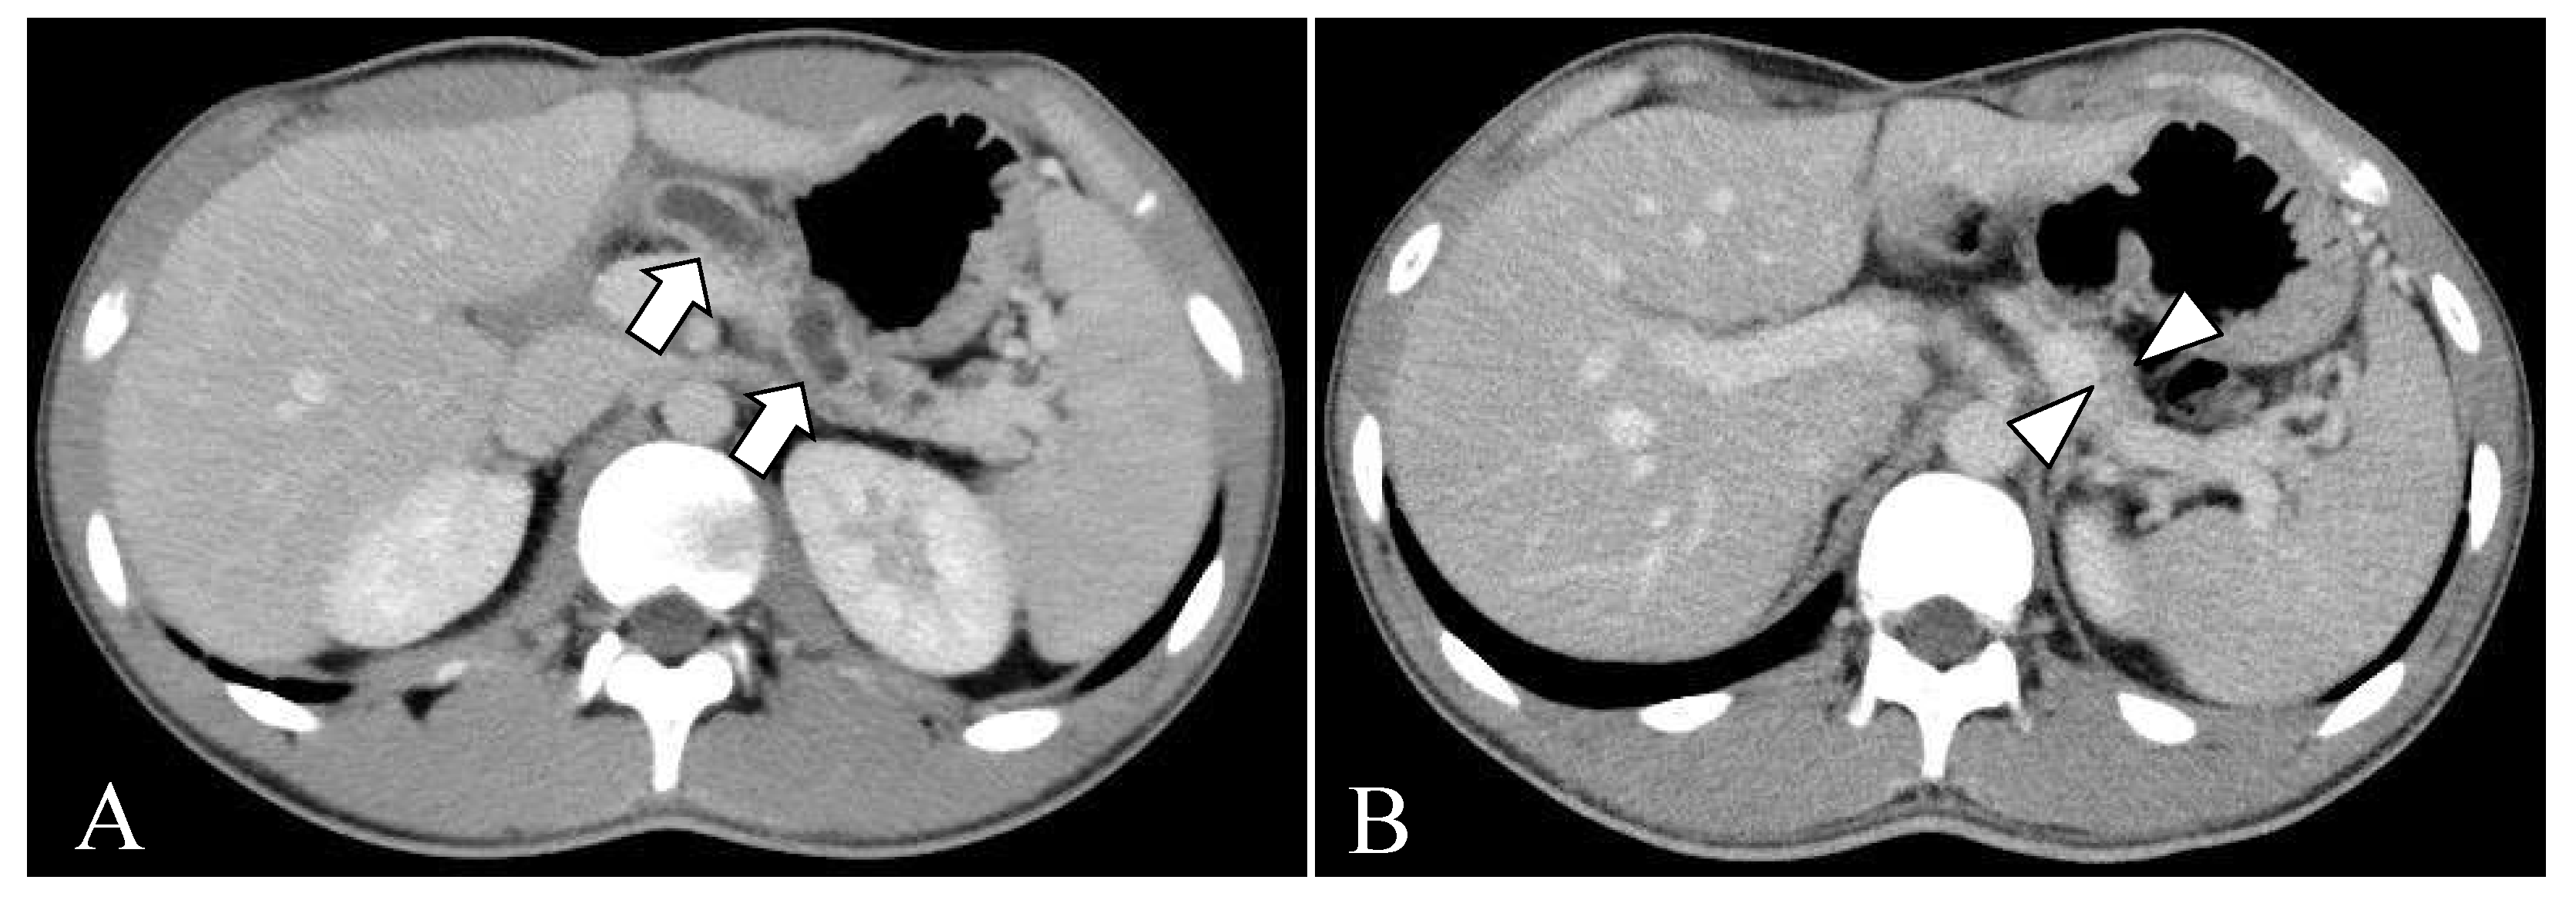

2.2. Clinical Course before Surgery

2.3. Surgical Treatment